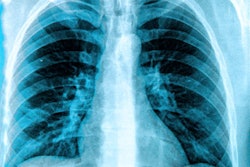

MRI is quite useful for identifying lung perfusion and ventilation impairment and assessing changes in the structure of lung parenchyma, Nyilas and colleagues explained. Previous research has suggested that functional MRI of the lungs could help identify early changes in ventilation and perfusion that aren't necessarily clear on traditional lung functional assessment tests.

They conducted a study that included 44 adults (10 were healthy control participants [never smokers], nine former tobacco smokers, 13 electronic nicotine device users, and 12 active tobacco smokers) who underwent lung function tests and noncontrast functional MRI scans before (MRI 1) and after (MRI 2) using vaping devices or smoking tobacco. Baseline assessment was performed after at least two hours of abstinence from vaping or smoking; the team measured lung perfusion and fractional ventilation impairment as percentages of affected lung volume.

(A-C) Example of pulmonary perfusion images obtained by using noncontrast-enhanced matrix pencil MRI in three different tobacco smokers before exposure (preexposure) and after exposure (postexposure). The images before and after exposure were acquired at corresponding coronal section locations. Arrows indicate lung regions with decreased regional perfusion after the exposure to nicotine. Red corresponds to high values of ventilation amplitude and perfusion amplitude, whereas blue corresponds to low values. Images and caption courtesy of the RSNA.Electronic cigarette (e-cigarette) users demonstrated a reduction in the percentage of lung impairment after exposure (which can impact ventilation) on the second MRI scan. In tobacco smokers, however, there was a decrease in lung perfusion after exposure (which impacts blood flow in the lungs), as indicated by a higher percentage of lung impairment. These were the only results that were statistically significant.